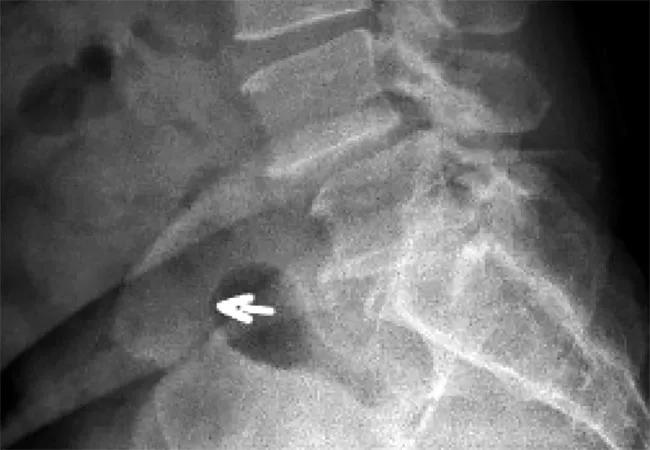

16-NEU-941-Benzel-Inset

X-rays demonstrating an L4-5 slip in a patient with lumbar stenosis.